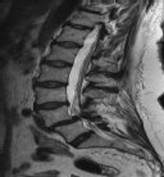

Figures 1 and 2 show sagittal and axial MRI from an 83-year-old woman with an ataxic gait, loss of dexterity, and intermittent loss of bowel and bladder control. The symptoms have been getting progressively worse over the past several weeks.

What disease process is most likely the cause of the patient’s symptoms?

4. Pigmented villonodular synovitis Discussion: B

The patient has a pannus at the C1-2 articulation that is compressing the spinal cord and causing myelopathy symptoms. The development of a pannus at this location has been associated with rheumatoid arthritis. Steinberger and associates showed increased morbidity and mortality when using an anterior approach and the surgery took longer than 4 hours. Chieng and associates showed better outcomes and lower complications rates using a posterior approach.